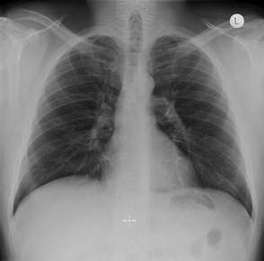

А) Б)

Рис 1. Рентгенограммы легких: а) взрослого мужчины; б) ребенка.

При рентгенологическом исследовании грудной клетки ясно видны два светлых «легочных поля», по которым судят о легких, так как вследствие наличия в них воздуха они легко пропускают рентгеновские лучи и дают просветления. Оба легочных поля отделены друг от друга интенсивной срединной тенью, образуемой грудиной, позвоночником, сердцем и крупными сосудами. Эта тень составляет медиальную границу легочных полей; верхняя и латеральная границы образованы ребрами. Снизу находится диафрагма.

Верхняя часть легочного поля пересекается с ключицей, которая отделяет надключичную область от подключичной. Ниже ключицы на легочное поле наслаиваются пересекающиеся между собой передние и задние части ребер. Они располагаются косо: передние отрезки – сверху вниз и медиально; задние – сверху вниз и латерально. Хрящевые части передних отрезков ребер при рентгеновском исследовании не видны. Для определения различных пунктов легочного поля пользуются промежутками между передними отрезками ребер (межреберья).

Собственно легочная ткань видна в светлых ромбовидных межреберьях. В этих местах виден сетевидный или пятнистый рисунок, состоящий из более или менее узких тяжеобразных теней, наиболее интенсивных в области корней легких и постепенно убывающих в своей интенсивности от срединной тени сердца к периферии легочных полей. Это так называемый легочный рисунок. По обе стороны тени сердца на протяжении передних отрезков II – V ребер располагаются интенсивные тени корней легких. От тени сердца они отделены небольшой тенью главных бронхов. Тень левого корня несколько короче и уже, так как она больше прикрывается тенью сердца, чем справа.

Анатомической основой тени корней и легочного рисунка является сосудистая система малого круга кровообращения – легочные вены и артерии с радиарно отходящими от них ветвями, рассыпающимися в свою очередь на мелкие веточки. Лимфатические узлы в норме не дают тени.

Анатомический субстрат легочного рисунка и теней корней особенно ясно заметен при томографии (послойной рентгенографии), которая дает возможность получить снимки отдельных слоев легкого без наслоения на легочное поле ребер. Легочной рисунок и корневые тени есть симптом нормальной рентгеновской картины легких в любом возрасте, включая и ранний детский. При вдохе видны просветления, соответствующие плевральным синусам.

Рентгенологический метод исследования позволяет видеть изменения в соотношениях органов грудной клетки, происходящие при дыхании. При вдохе диафрагма опускается, куполы ее уплощаются, центр передвигается несколько книзу. Ребра поднимаются, межреберные промежутки делаются шире, Легочные поля становятся светлее, легочный рисунок отчетливее. Плевральные синусы «просветляются», становятся заметными. Сердце приближается к вертикальному положению. При выдохе возникают обратные соотношения.